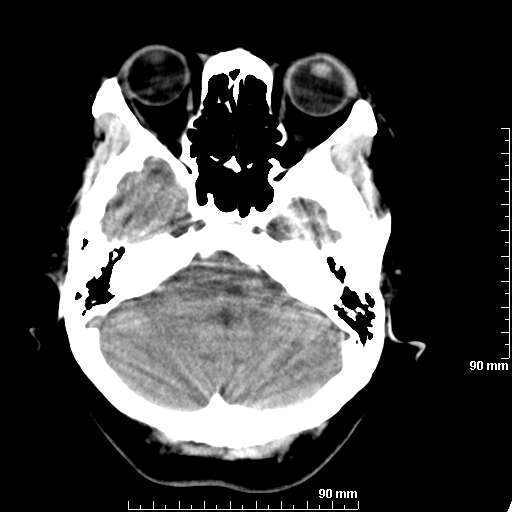

[维修案例解析] 大家猜猜看,这个伪影是怎样产生的.

我院西门子单排CT由于一零件受损而产生的伪影.

哈哈,都不是。是虑线器fiter裂损。大家没想到吧。

哦,跟脑出血有点像哦

形状不规则,边缘模糊。比较特殊的一种伪影哈!

这种伪影很常见!伪影应该是在视野的中心的。

西门子的虑线器fiter裂损这才是很难见的问题,GE的最常见

虑线器老化,中间崩裂一块掉了